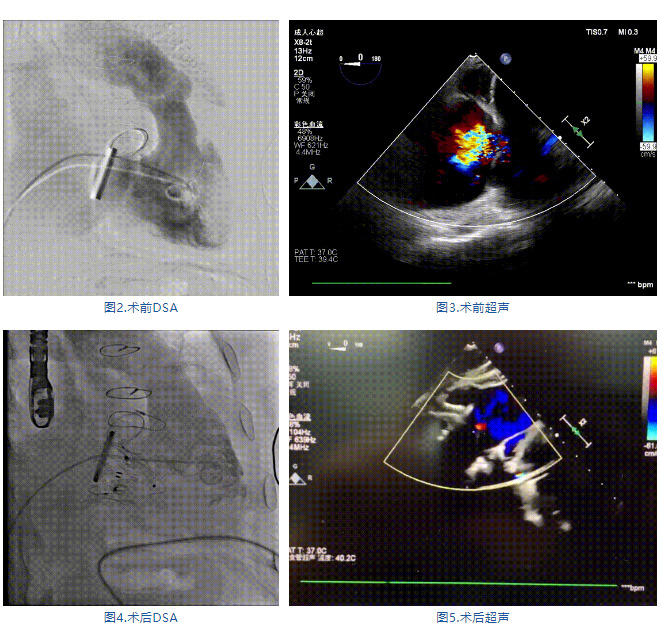

手術(shù)在全麻狀態(tài)下進(jìn)行,郭惠明教授團隊采用經(jīng)右側(cè)頸靜脈入路的方式送入輸送器進(jìn)入體內(nèi),并在TEE和DSA的指引下進(jìn)行。在輸送器進(jìn)入右室后釋放室間隔錨定裝置,旋轉(zhuǎn)輸送器,使得錨定裝置對準(zhǔn)室間隔面;而后釋放前瓣夾持件,確定夾持件位于右室側(cè)釋放LuX-Valve Plus人工瓣膜盤片,再使用DSA和超聲確認(rèn)盤片是否位于右房側(cè),同時調(diào)整瓣膜的同軸性。緊接著在DSA和超聲的監(jiān)視下調(diào)整室間隔錨定件貼合室間隔,釋放室間隔錨定裝置。再次確認(rèn)瓣膜的穩(wěn)定性和同軸性后,將輸送器撤出體內(nèi),最終完成LuX-Valve Plus人工瓣膜植入(圖2-5),手術(shù)獲得圓滿成功。患者在手術(shù)室即刻拔除氣管插管,術(shù)后超聲提示LuX-Valve Plus人工三尖瓣瓣膜同軸性良好,瓣架固定牢靠,無反流和瓣周漏。